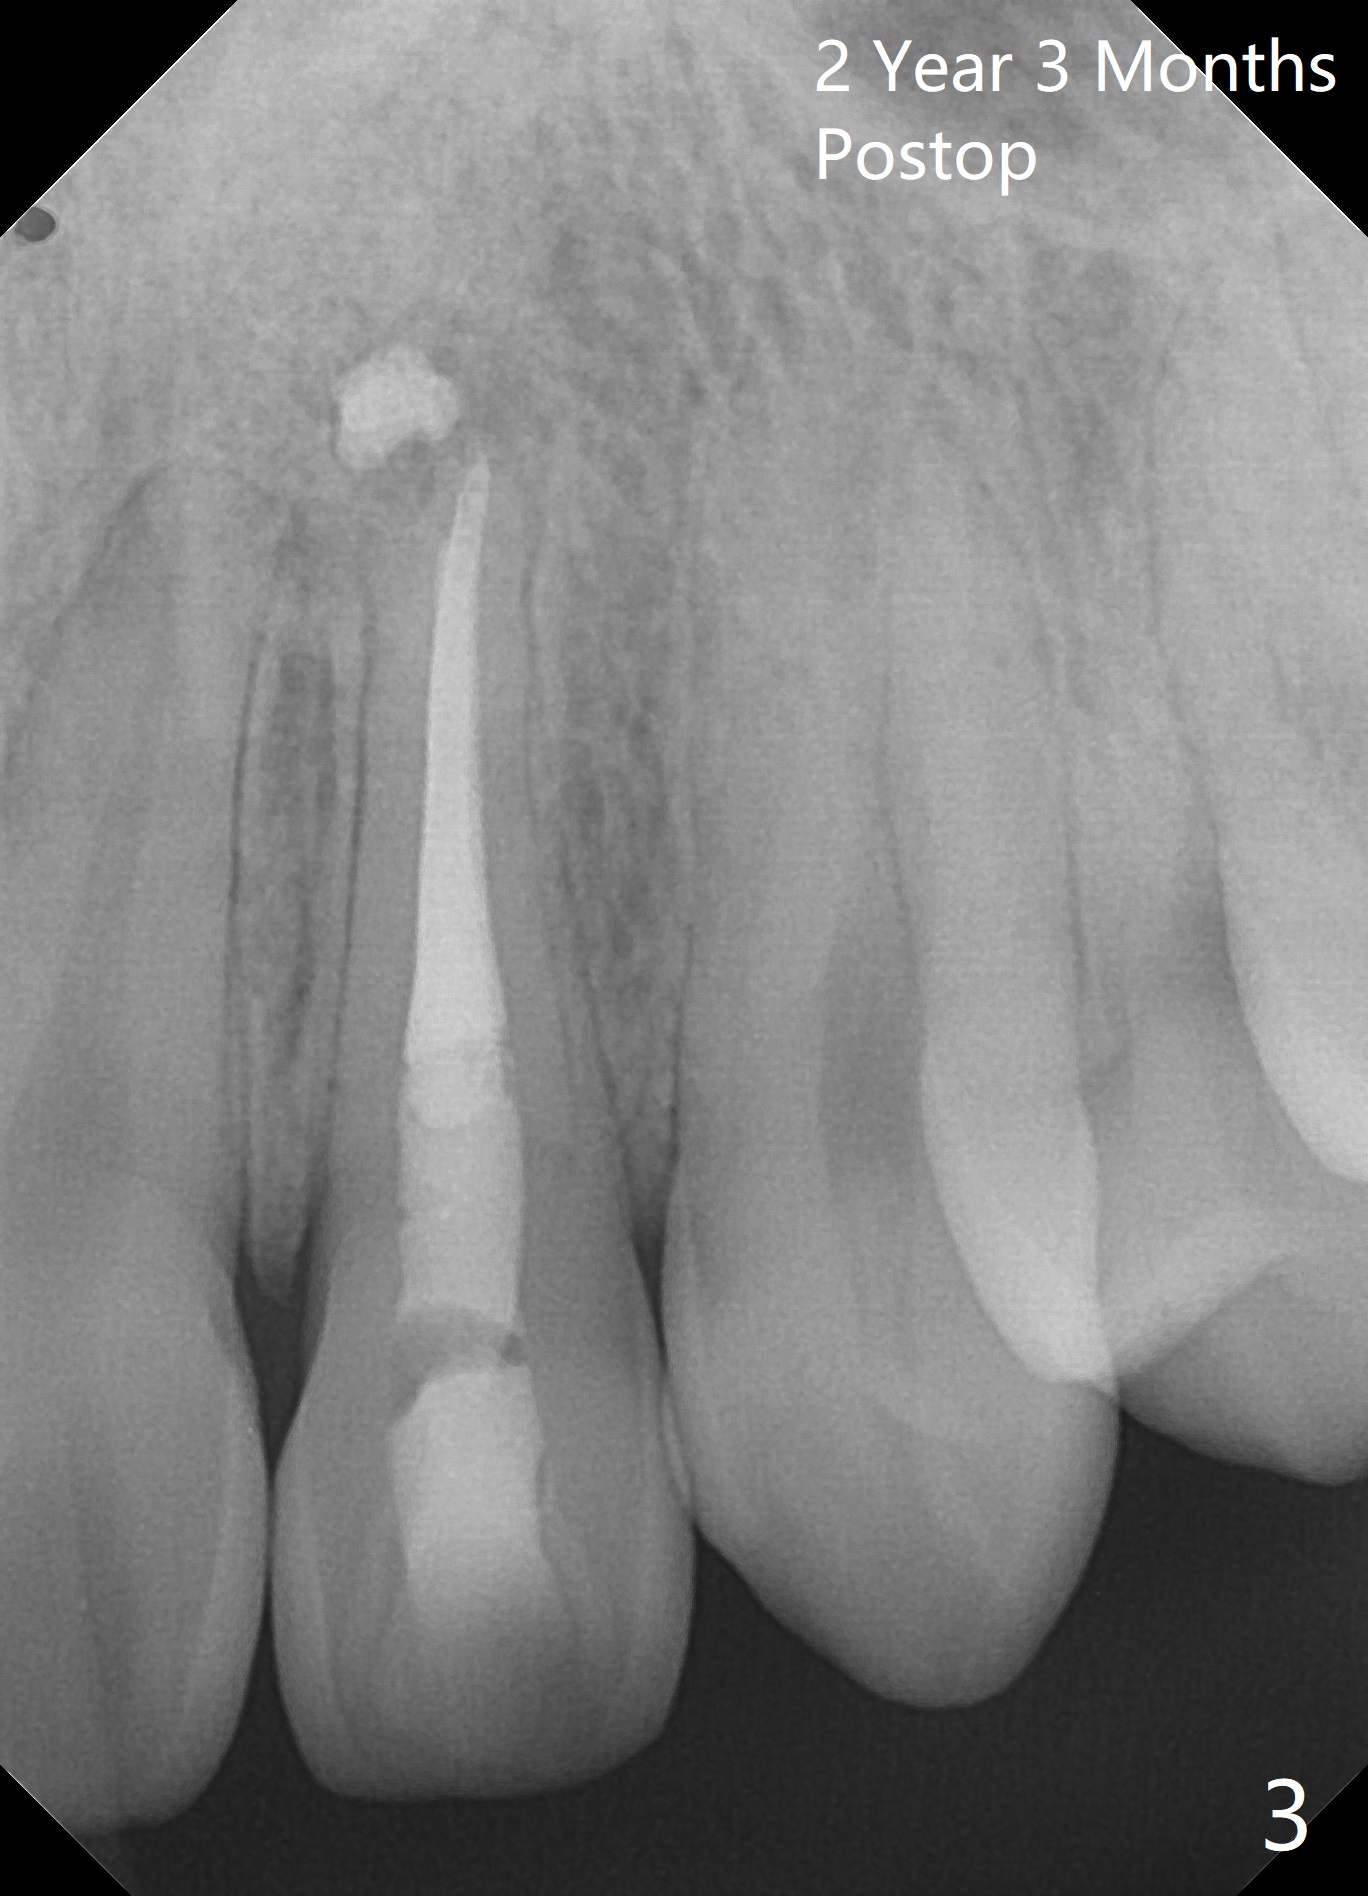

A 18-year-old man develops acute apical periodontitis at #10 several years after phase I and II orthodontic treatment. Fig.1 is taken immediately post RCT with #70 master gutta percha (GP) and 2 medium and 1 fine fine accessory GP. Periapical radiolucency reduces 1 year 9 months postop (Fig.2). The patient reports occasional tingling 2 years 3 months postop (Fig.3).